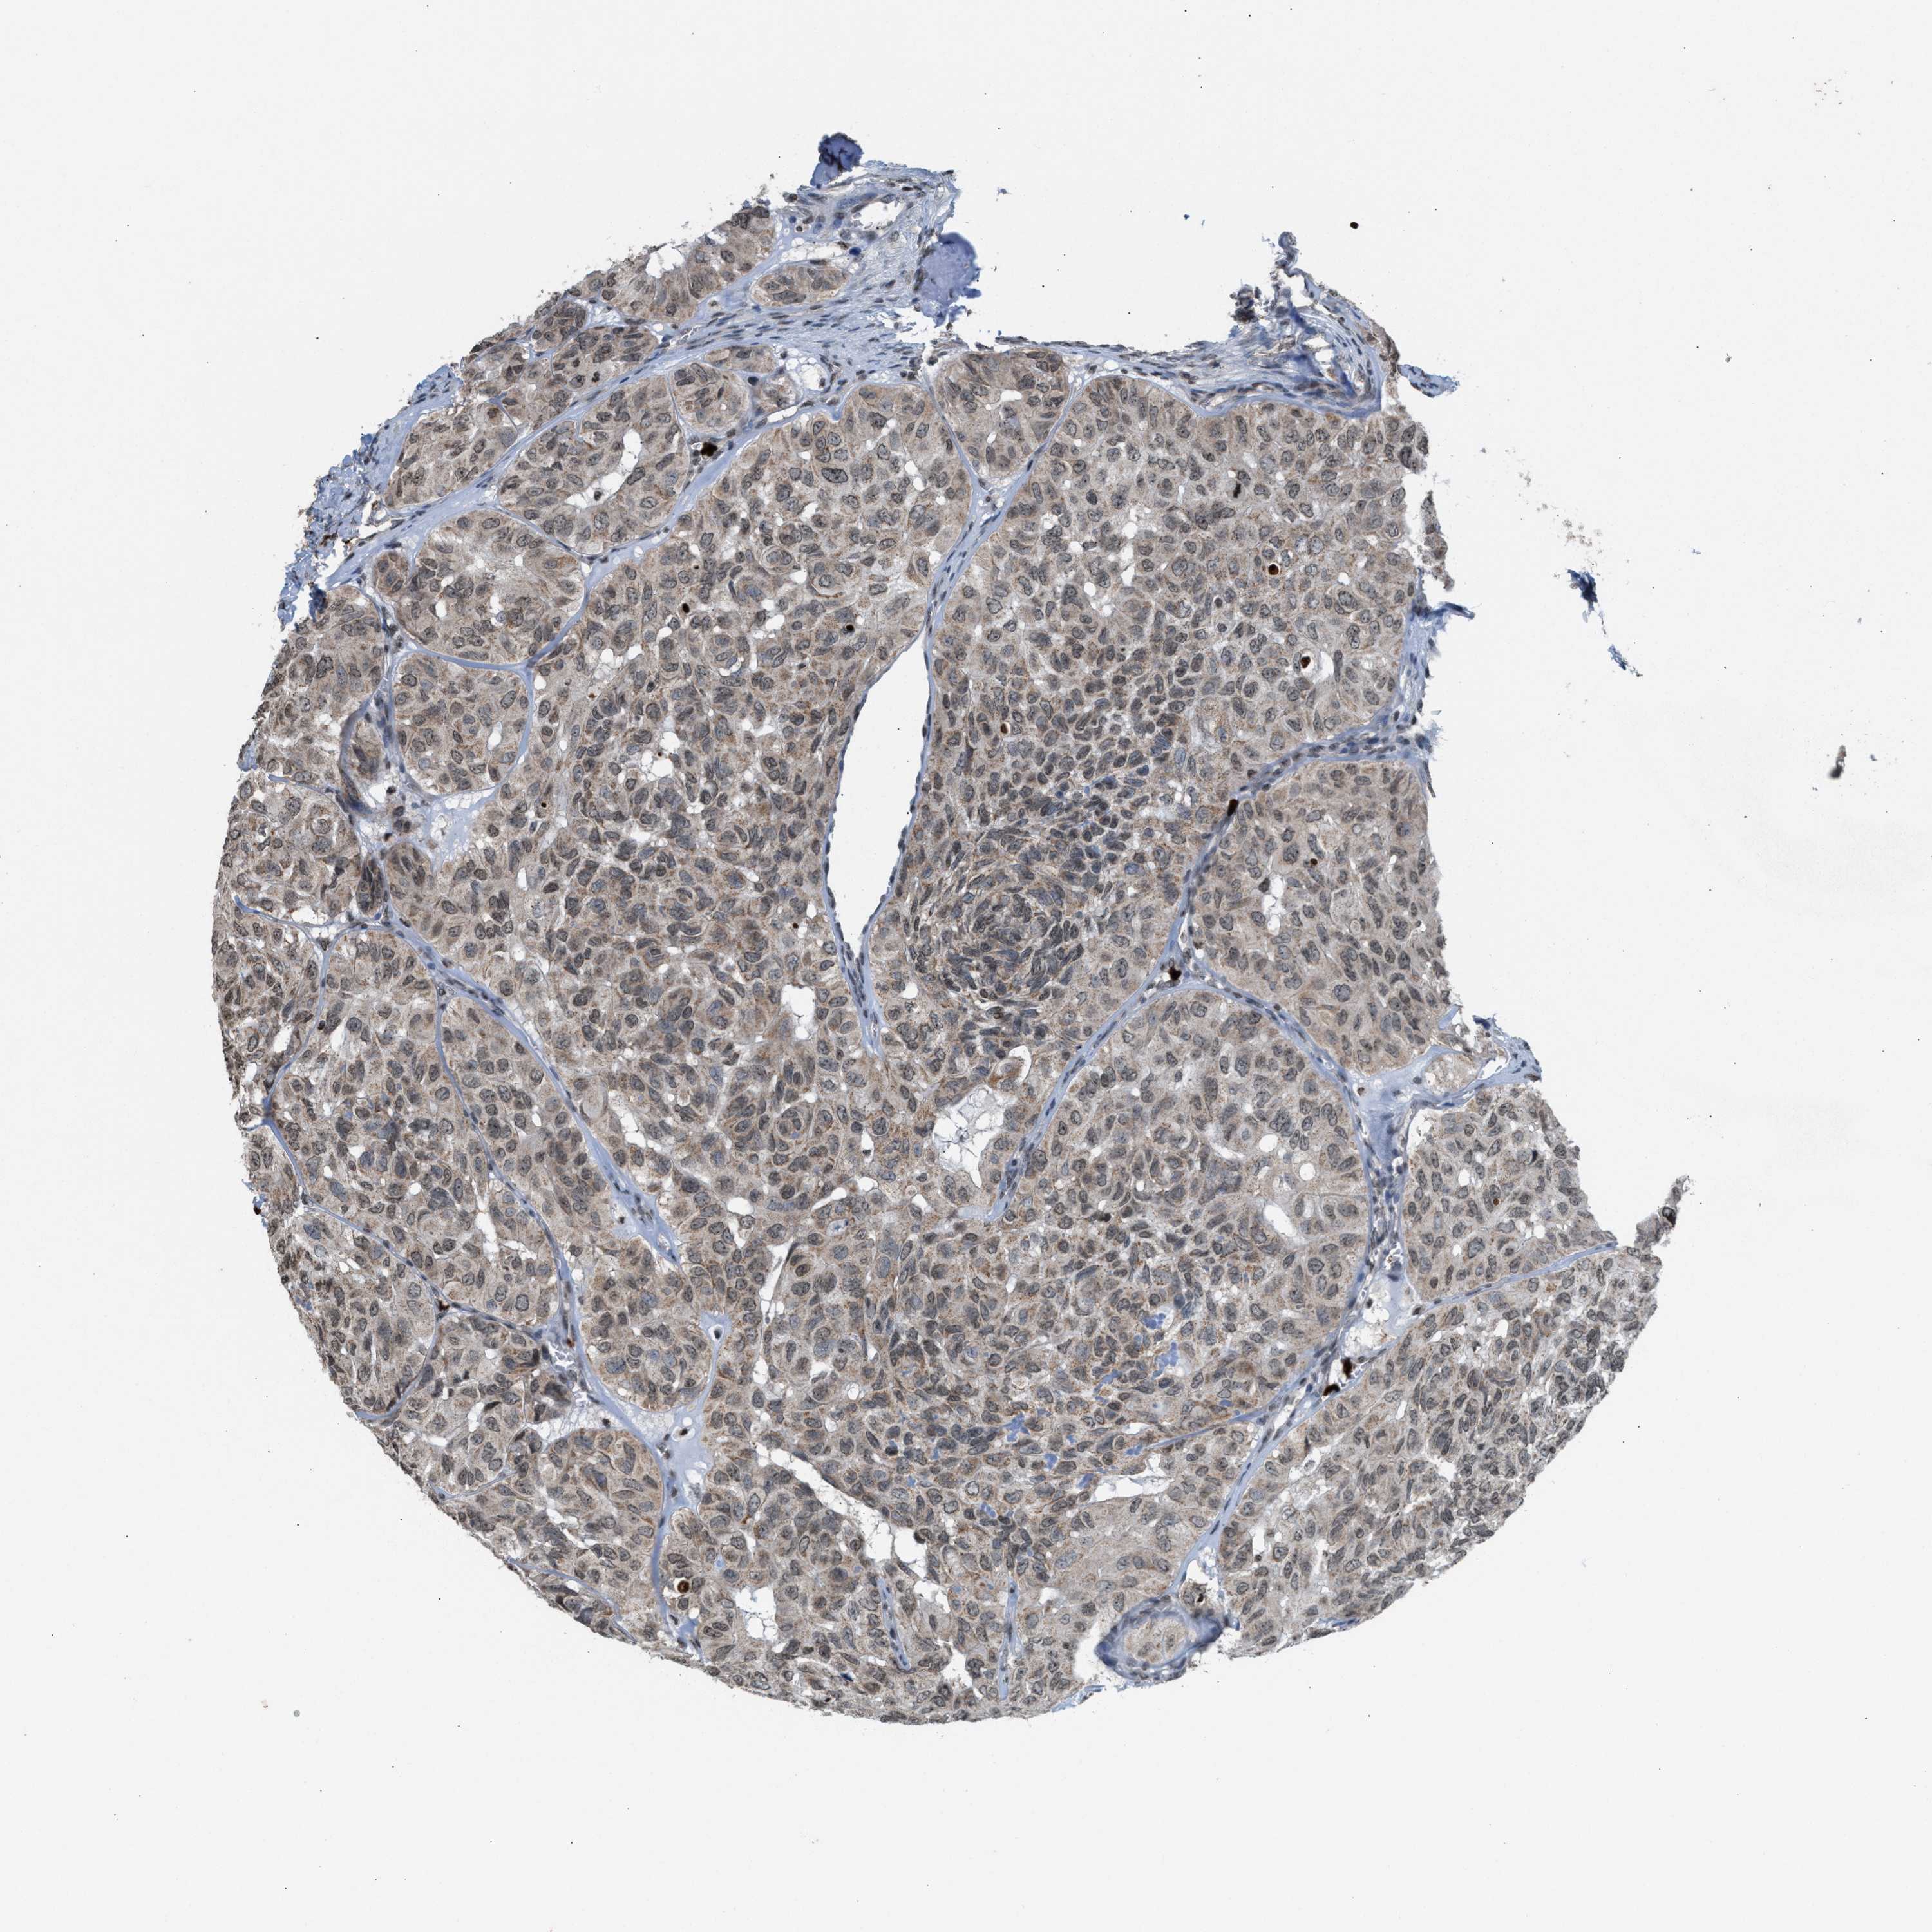

HEAD AND NECK CANCER - Protein expressioni

A mouse-over function shows sample information and annotation data. Click on an image to view it in a full screen mode. Samples can be filtered based on level of antibody staining by selecting one or several of the following categories: high, medium, low and not detected. The assay and annotation is described here.

Antibody stainingi

Antibody staining in the annotated cell types in the current human tissue is reported as not detected, low, medium, or high, based on conventional immunohistochemistry profiling in selected tissues. This score is based on the combination of the staining intensity and fraction of stained cells.

Each image is clickable and will lead to virtual microscopy that enables deeper exploration of all samples and also displays staining intensity scores, fraction scores and subcellular localization as well as patient and tissue information for each sample.

Antibody HPA022470

Staining

High

Medium

Low

Not detected

Intensity

Strong

Moderate

Weak

Negative

Quantity

>75%

75%-25%

<25%

None

Location

Nuclear

Cytoplasmic/membranous

Cytoplasmic/membranous,nuclear

Squamous cell carcinoma, NOS